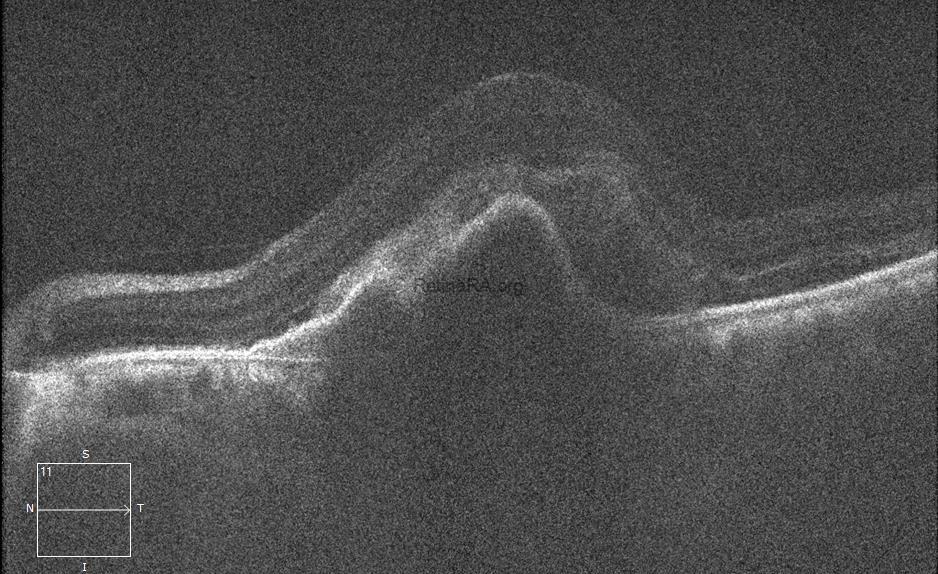

A RPE tear developed after 1st aflibercept injection. RPE tear is breaking off the RPE of a PED on one side and folding over on itself on the opposite side. A double layer of RPE at the fovea does not cause decreased visual acuity, but if the area without RPE includes the fovea, visual acuity is severely reduced. The visual acuity of this patient improved to 20/70 because the fovea was not affected by the absence of RPE. The bare choroidal area (the area without RPE) appears red on the color photograph and distinctly hypoautofluorescent on the autofluorescent image. On the foveal horizontal OCT scan, the retracted RPE is seen as a dense hyperreflective tissue due to duplication of the RPE, and a shadowing effect beneath it. The OCT image scanning the inferior of the fovea depicts the absence of RPE. In the absence of RPE, the bare choroid area shows hyperreflectivity as a result of deeper penetration.